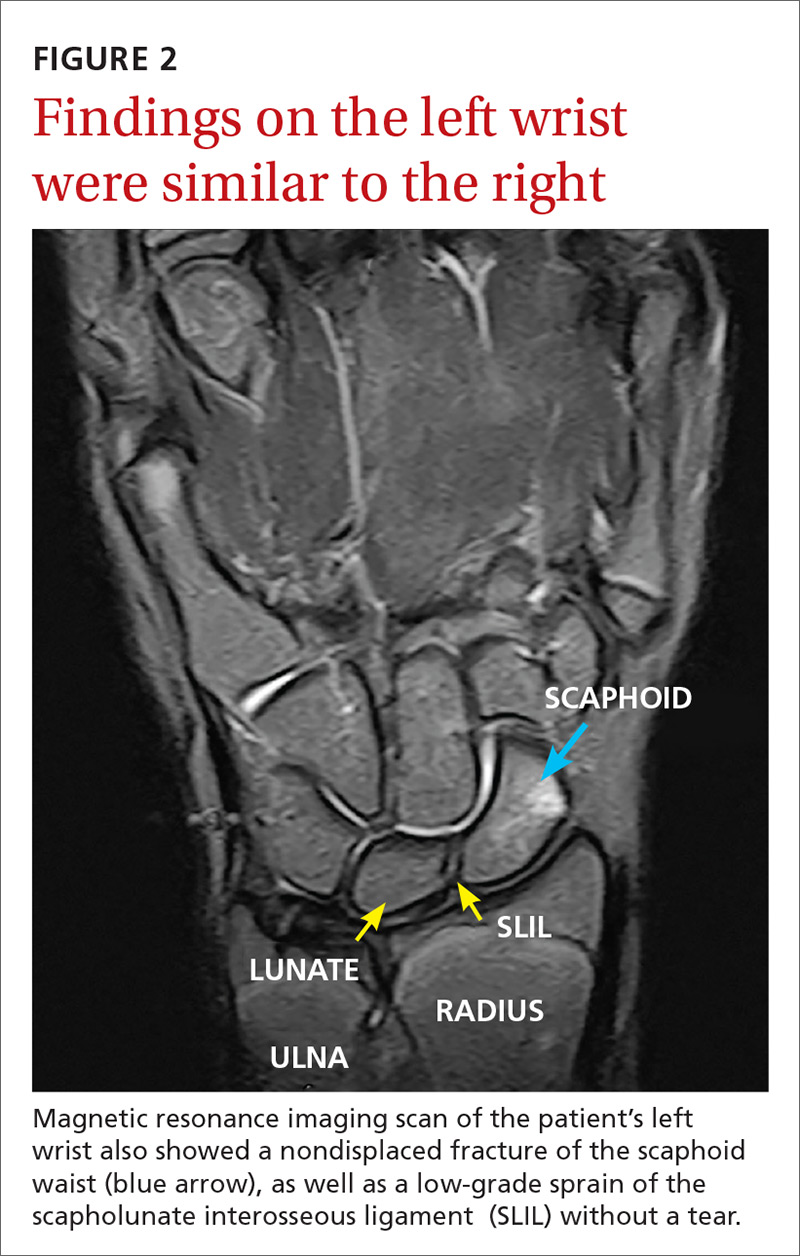

The MRI revealed bilateral, nondisplaced, extra-articular fractures extending through the scaphoid waist, with surrounding bone marrow edema. In the right wrist, the patient also had a low-grade partial tear of the membranous portion of the scapholunate interosseous ligament (SLIL) at the scaphoid attachment (FIGURE 1). In the left wrist, she also had a low-grade sprain of the SLIL without tear (FIGURE 2).